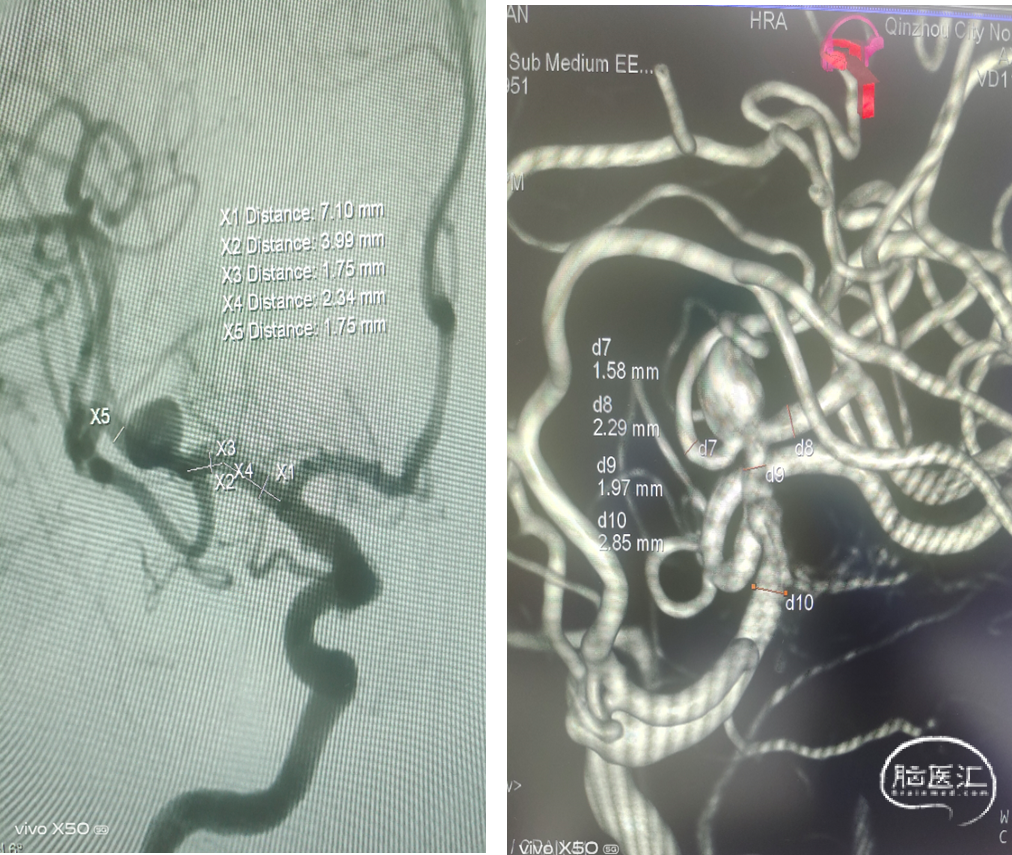

原位释放,释放过程头端导丝无移位,无需推拉即可打开并贴壁:自动挡FD!

1、定位精准、原位释放:首个显影标记对准支架落点:放在定位点附近即可原位释放, 简化操作、免支架拖拽、减少血管损伤和支架扭结;全程多个显影标记可视化支架释放进程:完全掌握手术操作,安全性高;

2、全程辅助支架打开、远端导丝不位移: 机械球囊 • 自动膨胀:全程辅助支架打开、无需推挤;• 分段吸收张力:释放时导丝头端稳定、不前蹿,操作安全;

3、易回收,可完全回收至支架保护鞘: 支架尾端结构:

•可体内回收:解脱点前可完全回收,重新定位释放;

•必要情况下,可回收至无菌支架保护鞘:重新进入微导管操作 首个显影标记对准支架落点 回收标记 机械球囊所在位置。